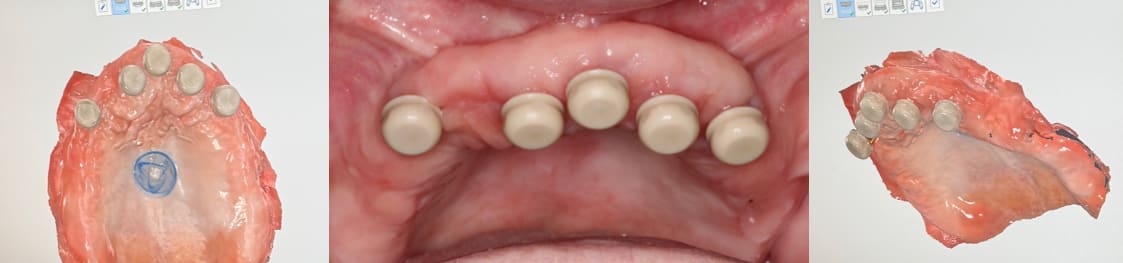

Due to the angulation of the implant placement, a 15-degree angled LOCATOR abutment was placed (Figure 5 and Figure 6). Angulation pins were passively placed into the LOCATOR abutments to determine proper spacing (Figure 7). The existing maxillary and mandibular appliances were scanned (fastcscan io™ with Medit® i700®, Glidewell) for the laboratory to design the initial try-in appliance prior to milling of the final zirconia LOCATOR FIXED® prosthesis (Figure 8). LOCATOR scan bodies were placed, and the LOCATOR level digital impression was made (Figure 9).